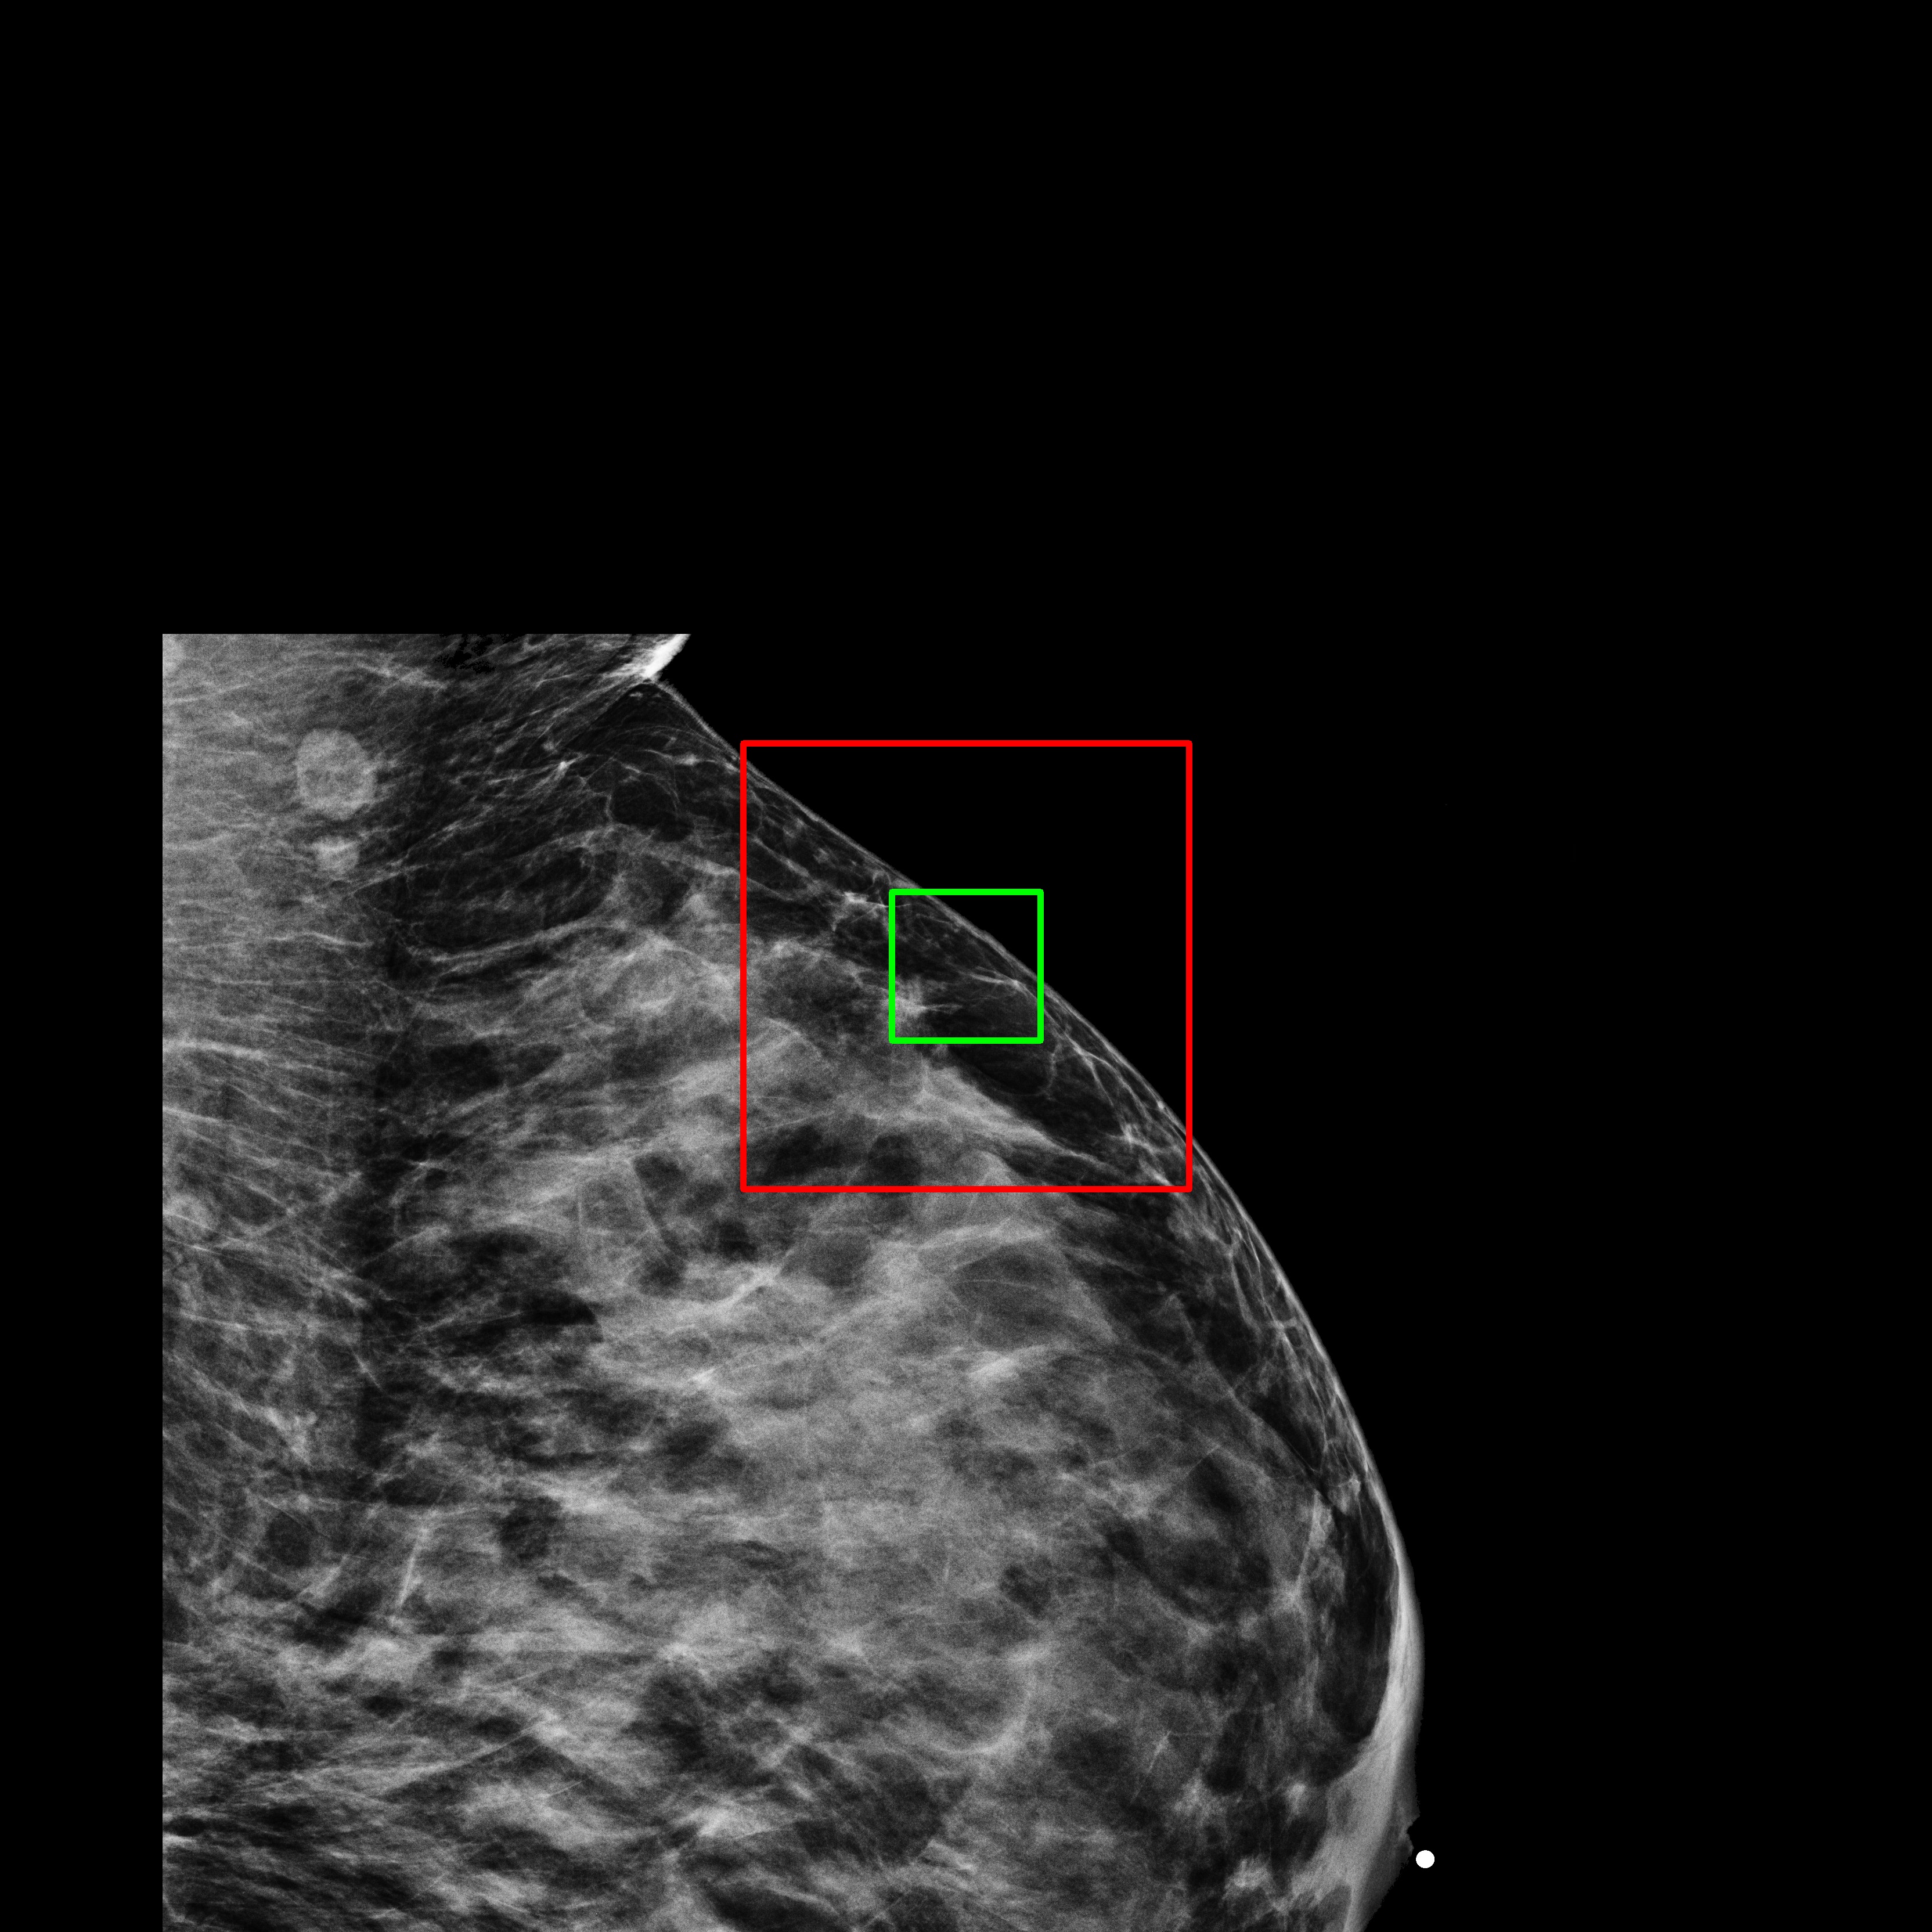

4.1.3 Qualitative Results

The baseline for this task is a single-channel U-Net-based DDPM trained on full-resolution -pixel patches extracted from mammograms. This model learns patch characteristics but performs poorly in image reconstruction tasks. Even if the patch is not generated from pure noise but from the partially noisy patch of an original image, the reconstruction is poor, as shown in Fig. 3(c).

What MAMBO can achieve in terms of qualitative results is presented in Fig. 1 and Fig. 3(d). MAMBO is able to generate high-quality images that are visually indistinguishable from the originals, representing plausible mammogram data to layman eyes. Results are also validated with expert radiologists, with quantitative results shown in Sec. 4.2.

Fig. 3(d) illustrates what MAMBO can achieve in terms of whole mammogram generation. When using global and local context data extracted from an original image, the denoised image (Fig. 3(b)) is difficult to distinguish from the original (shown in Fig. 3(a)). When providing only the original global context and generating local context and target patches from noise, we still observe good results, as we show in Fig. 3(d).